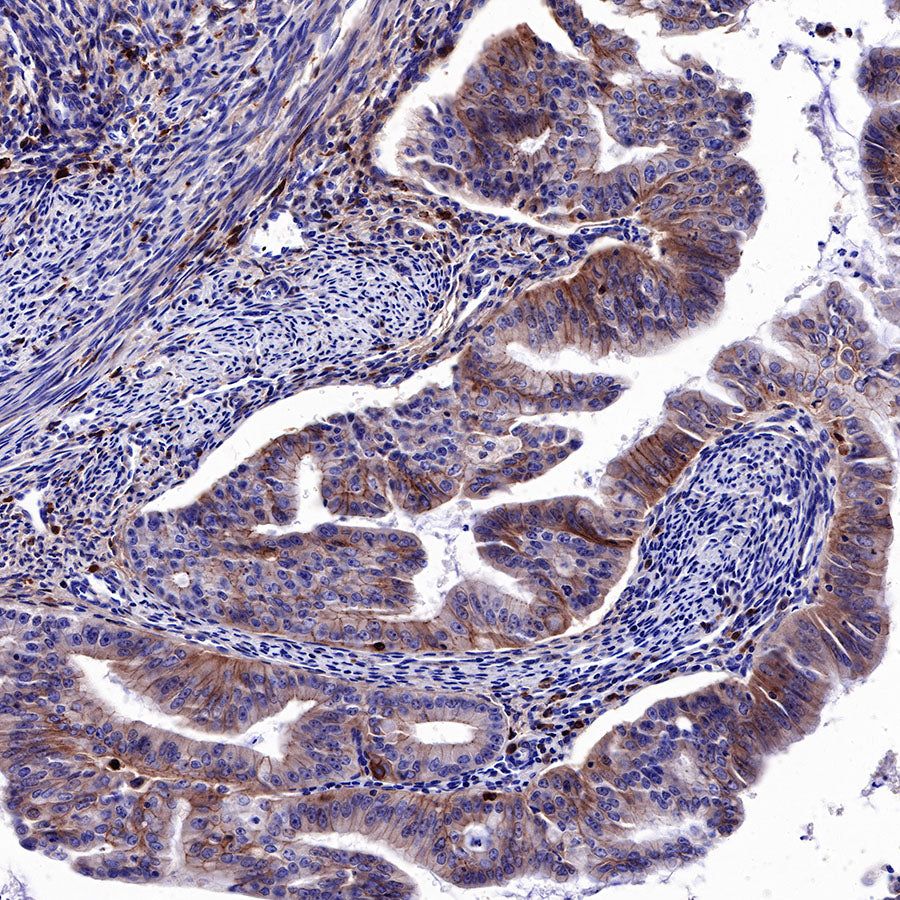

IHC shows positive staining in paraffin-embedded human endometrial cancer. Anti-EGFR antibody was used at 1/2000 dilution, followed by a HRP Polymer for Mouse & Rabbit IgG (ready to use). Counterstained with hematoxylin. Heat mediated antigen retrieval with Tris/EDTA buffer pH9.0 was performed before commencing with IHC staining protocol.